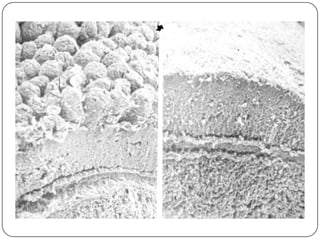

Jejuno Normal

Cólon

Detalhes